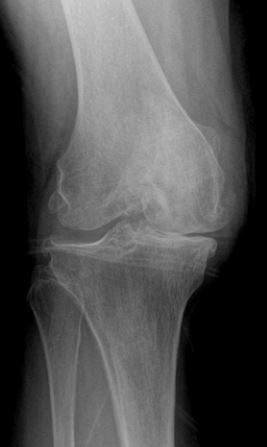

Bone on Bone Osteoarthritis of the Knee

When is a knee replacement needed?

Osteoarthritis is the diseases process of cartilage wear over a lifetime. When the cartilage is worn down to bone the osteoarthritis is considered end-stage. At this stage there is significant decrease in quality of life and function, then a knee replacement is warranted.

Who qualifies for a knee replacement?

Patients who have severe osteoarthritis, restrictions in function, and decrease in quality of live are candidates for knee replacement. A patient must be healthy enough to tolerate the procedure.